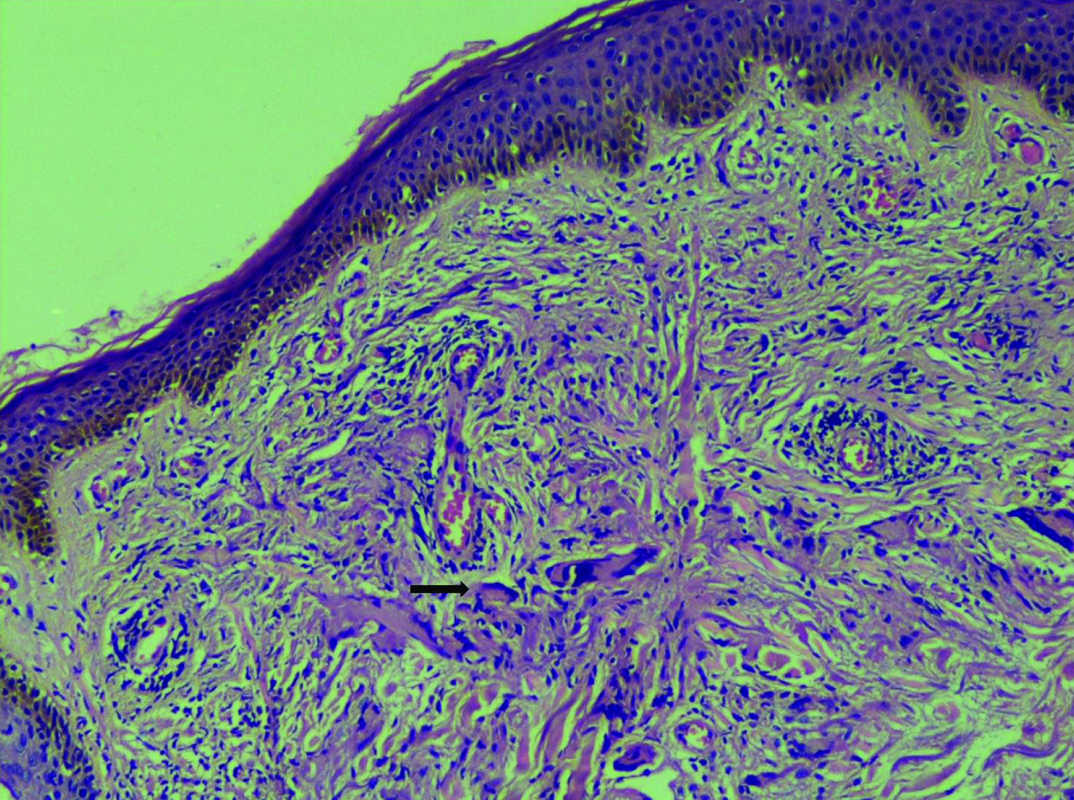

Histopathological examination with H & E stain revealed epidermis with focally thinned out areas upper and middle dermis with histiocytic aggregates surrounded by multiple giant cells. Focal areas of chronic inflammatory cells were seen [Table/Fig-4]. PAS stain was negative for fungal elements. Verhoeff van Gieson stain showed some degenerate elastic fibres [Table/Fig-5].

Thinned epidermis with degenerated elastic fibres with histiocyte aggregates surrounded by multiple giant cells. [H & E stain. x100].